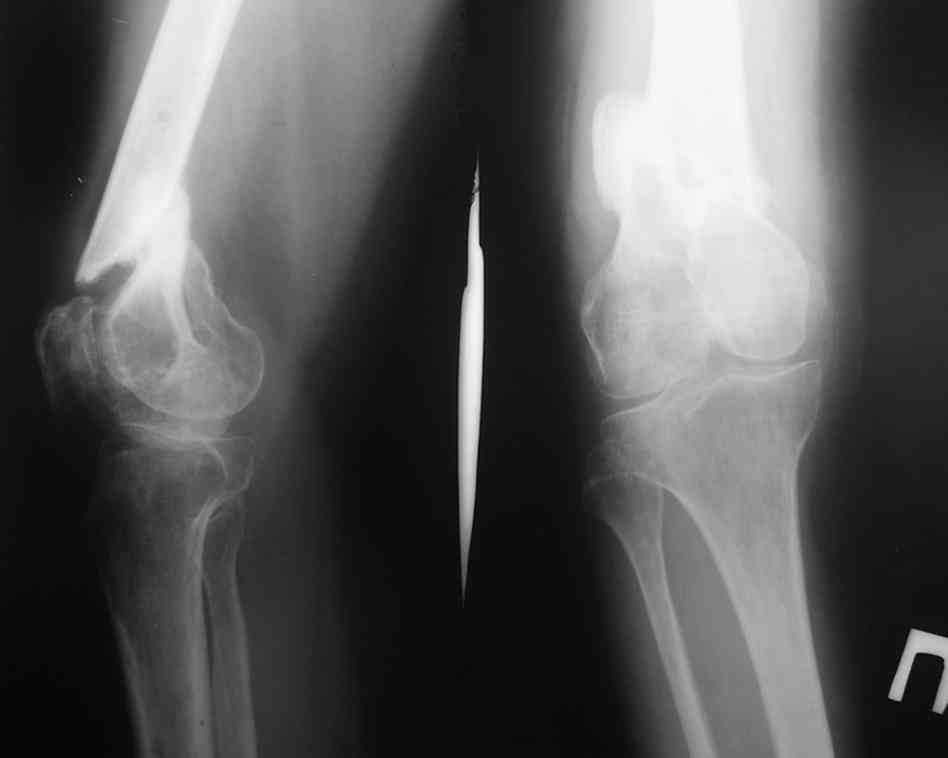

Больная К. с тугим ложным суставом н/3 бедра. Травма в 2005 г.-закрытый перелом, остеосинтез в аппарате Илизарова. В 2006 г. оперирована по поводу несросшегося перелома.

В ноябре 2006 г. демонтаж аппарата, после чего в течении месяца развилась вальгусная деформация. Имеется патологическая подвижность. Объем движений в коленном суставе 180-140. На обсуждение выносятся варианты лечения погружными конструкциями.

The patient with non-union of the distal femur. Trauma in 2005 - closed fracture of the femur, external fixation with Ilizarov apparatus. Non-union. In 2006 open reduction and external fixation with Ilizarov apparatus. In November 2006 the apparatus was removed, after that valgus deformation developed. There is pathological mobility. The knee motion 180-140. We'd like to discuss options of internal fixation.

Надо все-таки разобраться, что там местно - по снимку какое-то как будто сращение на ограниченном участке, но, как пишут, есть и патологическая подвиижность...

Если там сращние или тугой ожный сустав - можно лечить закрыто. Подправить аппаратом и либо заштифтовать, либо пластинку, можно с пластикой, Если дело ближе к болтающемуся ложному суставу - тогда открытая адаптация, аутопластика, как Михаил написал.

Согласен. По снимкам не похоже, чтоб сильно болталось, скорее даже срослось. Клинически с таким коротким фрагментом трудно оценить где "болтается" - в переломе или в суставе. Эффективно смотреть под ЭОПом в режиме скопии.